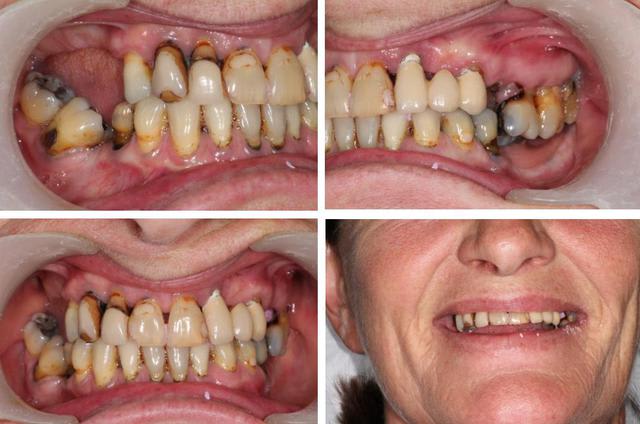

Autre cas qui peut poser un problème similaire .

Nouvelle patiente vu en urg pour resceller son bridge 22 24.

22 et 24 total recariées, tres mobiles.

je rescelle et on decide de se revoir pour faire le point.

55 ans, pour elle , pas question de rester sans dent, ni de dentier, même pendant 3 mois.

Mais sait pertinemment qu'elle est dans une situation... délicate !

Que peut on lui proposer ? doit on lui dire que l'on a pas de baguette magique ?

Voici les premieres photos. Peut être verra t'on une différence avec le cas de Jeff.